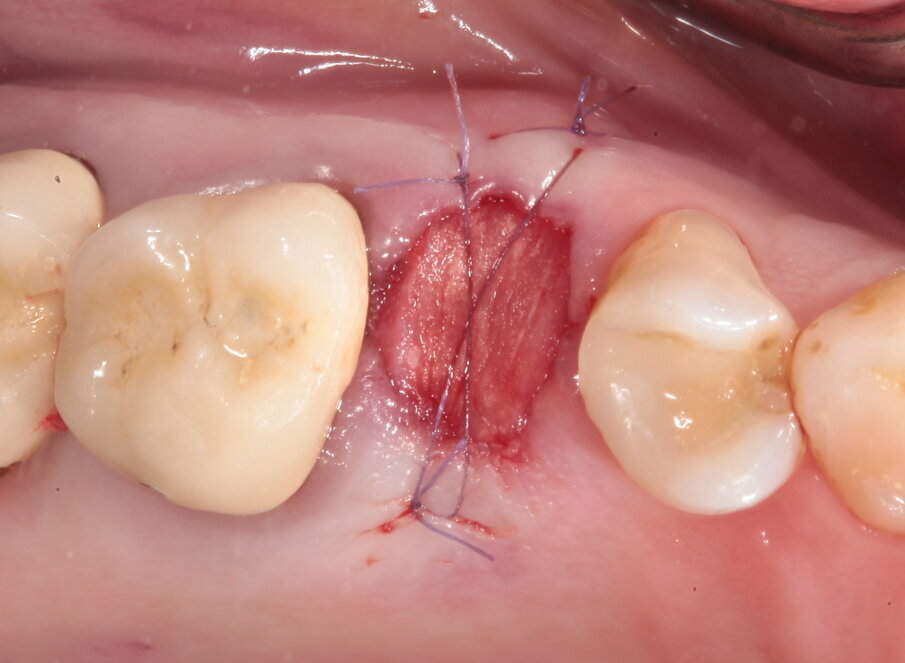

Viene disegnato un roll flap, posizionato l’impianto tramite una mascherina di guida per la fresa pilota ottenuta tramite stampa 3D, inserita una vite di guarigione transmucosa e suturato il lembo. Dalle immagini intraoperatorie si può notare come la scelta di materiale a rapido riassorbimento abbia permesso l’ottenimento di un osso vitale, sanguinante e con la quasi totale assenza di particelle di biomateriale ancora presenti. L’imprecisione nella sutura della porzione distale del lembo genererà uno spessore maggiorato del connettivo in quella zona, che avrà come effetto un piccolo inestetismo che tuttavia la paziente non nota e che non intende correggere (Figg. 14-17). Al termine dei 4 mesi necessari al completamento del processo di osteointegrazione, viene inserito un provvisorio avvitato con il quale inizia il condizionamento dei tessuti perimplantari.